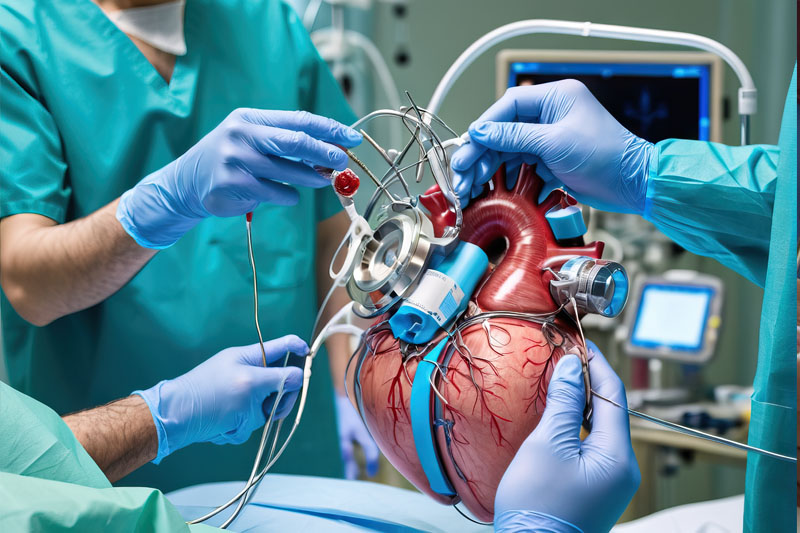

At Alliance Surgicals & Instruments, we are committed to delivering high-quality medical and surgical equipment that healthcare professionals trust. Our products are crafted with precision, ensuring safety, durability, and compliance with international standards.

- Premium Quality: Certified and reliable medical instruments.

- Innovation & Precision: Advanced technology for superior performance.